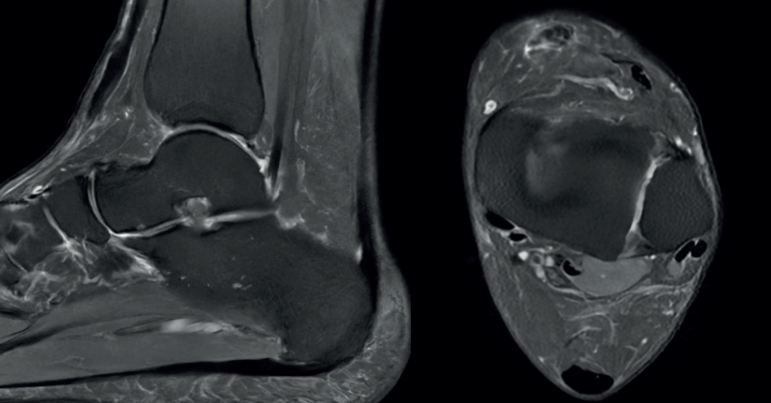

Figura 1. Corte sagital y axial de resonancia magnética donde se observa una rotura completa del tendón tibial anterior con retracción del cabo tendinoso.

Los estudios radiográficos no arrojaron anormalidades, mientras que la resonancia magnética reveló una desinserción completa del tendón TA con retracción hasta la articulación tibiotalar (Figura 1). Se decide un tratamiento quirúrgico de reanclaje tendinoso primario.